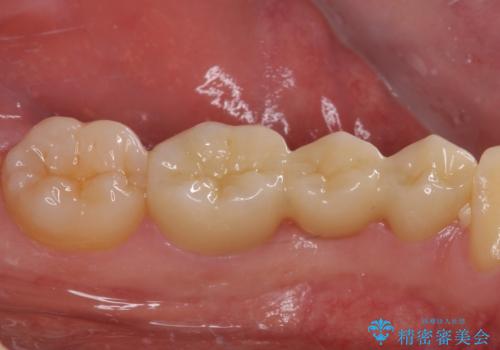

オールセラミックブリッジとしたことで、審美的かつ外れにくい補綴治療を行うことができました。